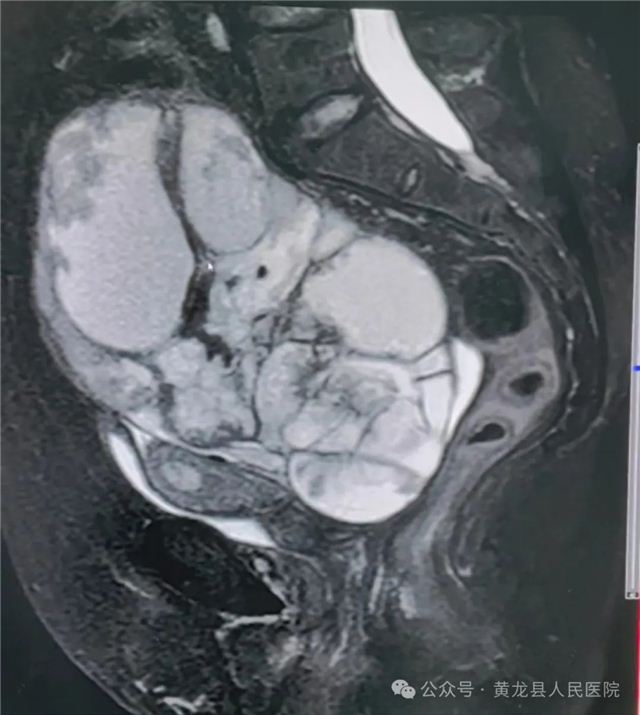

术前肿瘤影像图片

患者兰女士,70岁,发现下腹部包块4月,近1月包块明显增大,自觉腹胀,同时出现了尿频、尿急等症状,在家人的陪伴下来我院就诊寻求治疗。妇产科主任张海红接诊后,详细了解患者病史,并对患者进行查体时发现患者腹部隆起如孕4+月大小,B超和盆腔核磁共振提示盆腔内囊实性占位性病变,考虑卵巢来源囊腺癌可能,综合检验科相关检查,考虑腹部肿块为卵巢恶性肿瘤,必须尽快手术治疗,而且由于肿瘤巨大,患者的输尿管受到压迫,出现尿频尿急等症状,且患者年龄大,既往高血压20年,8年前因“右侧输卵管脓肿”外院行经腹腔镜右侧输卵管脓肿切开引流术,加之手术的应激状态和取瘤时血流动力学的急剧变化,对患者的心肺功能甚至生命都将是一次巨大的挑战。